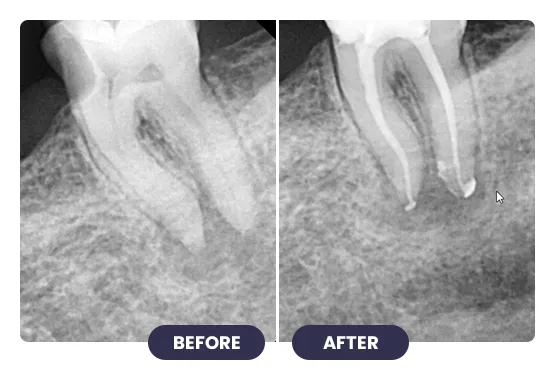

Treating infected or damaged teeth with root canal treatment at iCube Dental is a precise, technique-sensitive procedure that requires professional expertise and careful planning.

Advanced tools and methods are used to remove infection, clean the tooth canals, and restore tooth structure. This treatment relieves pain, prevents further infection, and preserves your natural tooth, ensuring proper bite and chewing function.